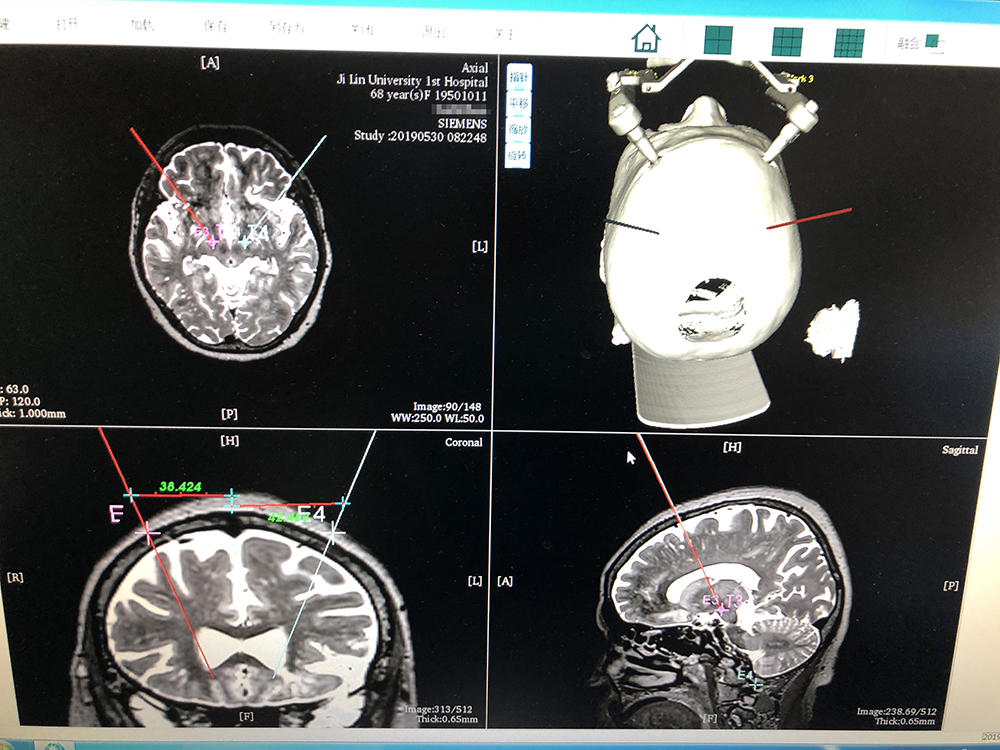

術(shù)前,邱吉慶教授借助“睿米”神經(jīng)外科手術(shù)機(jī)器人配套軟件,為患者制定雙側(cè) STN 核團(tuán)植入電極的手術(shù)路徑規(guī)劃。

借助“睿米”軟件制定手術(shù)規(guī)劃

手術(shù)規(guī)劃完成后,分別完成機(jī)械臂注冊(cè)和患者注冊(cè),系統(tǒng)顯示注冊(cè)精度分別達(dá)到0.07和0.16,符合 DBS 手術(shù)臨床的高精度要求。為進(jìn)一步確認(rèn),利用隨機(jī)驗(yàn)證點(diǎn)進(jìn)行精度驗(yàn)證,確認(rèn)誤差在1mm以內(nèi)。